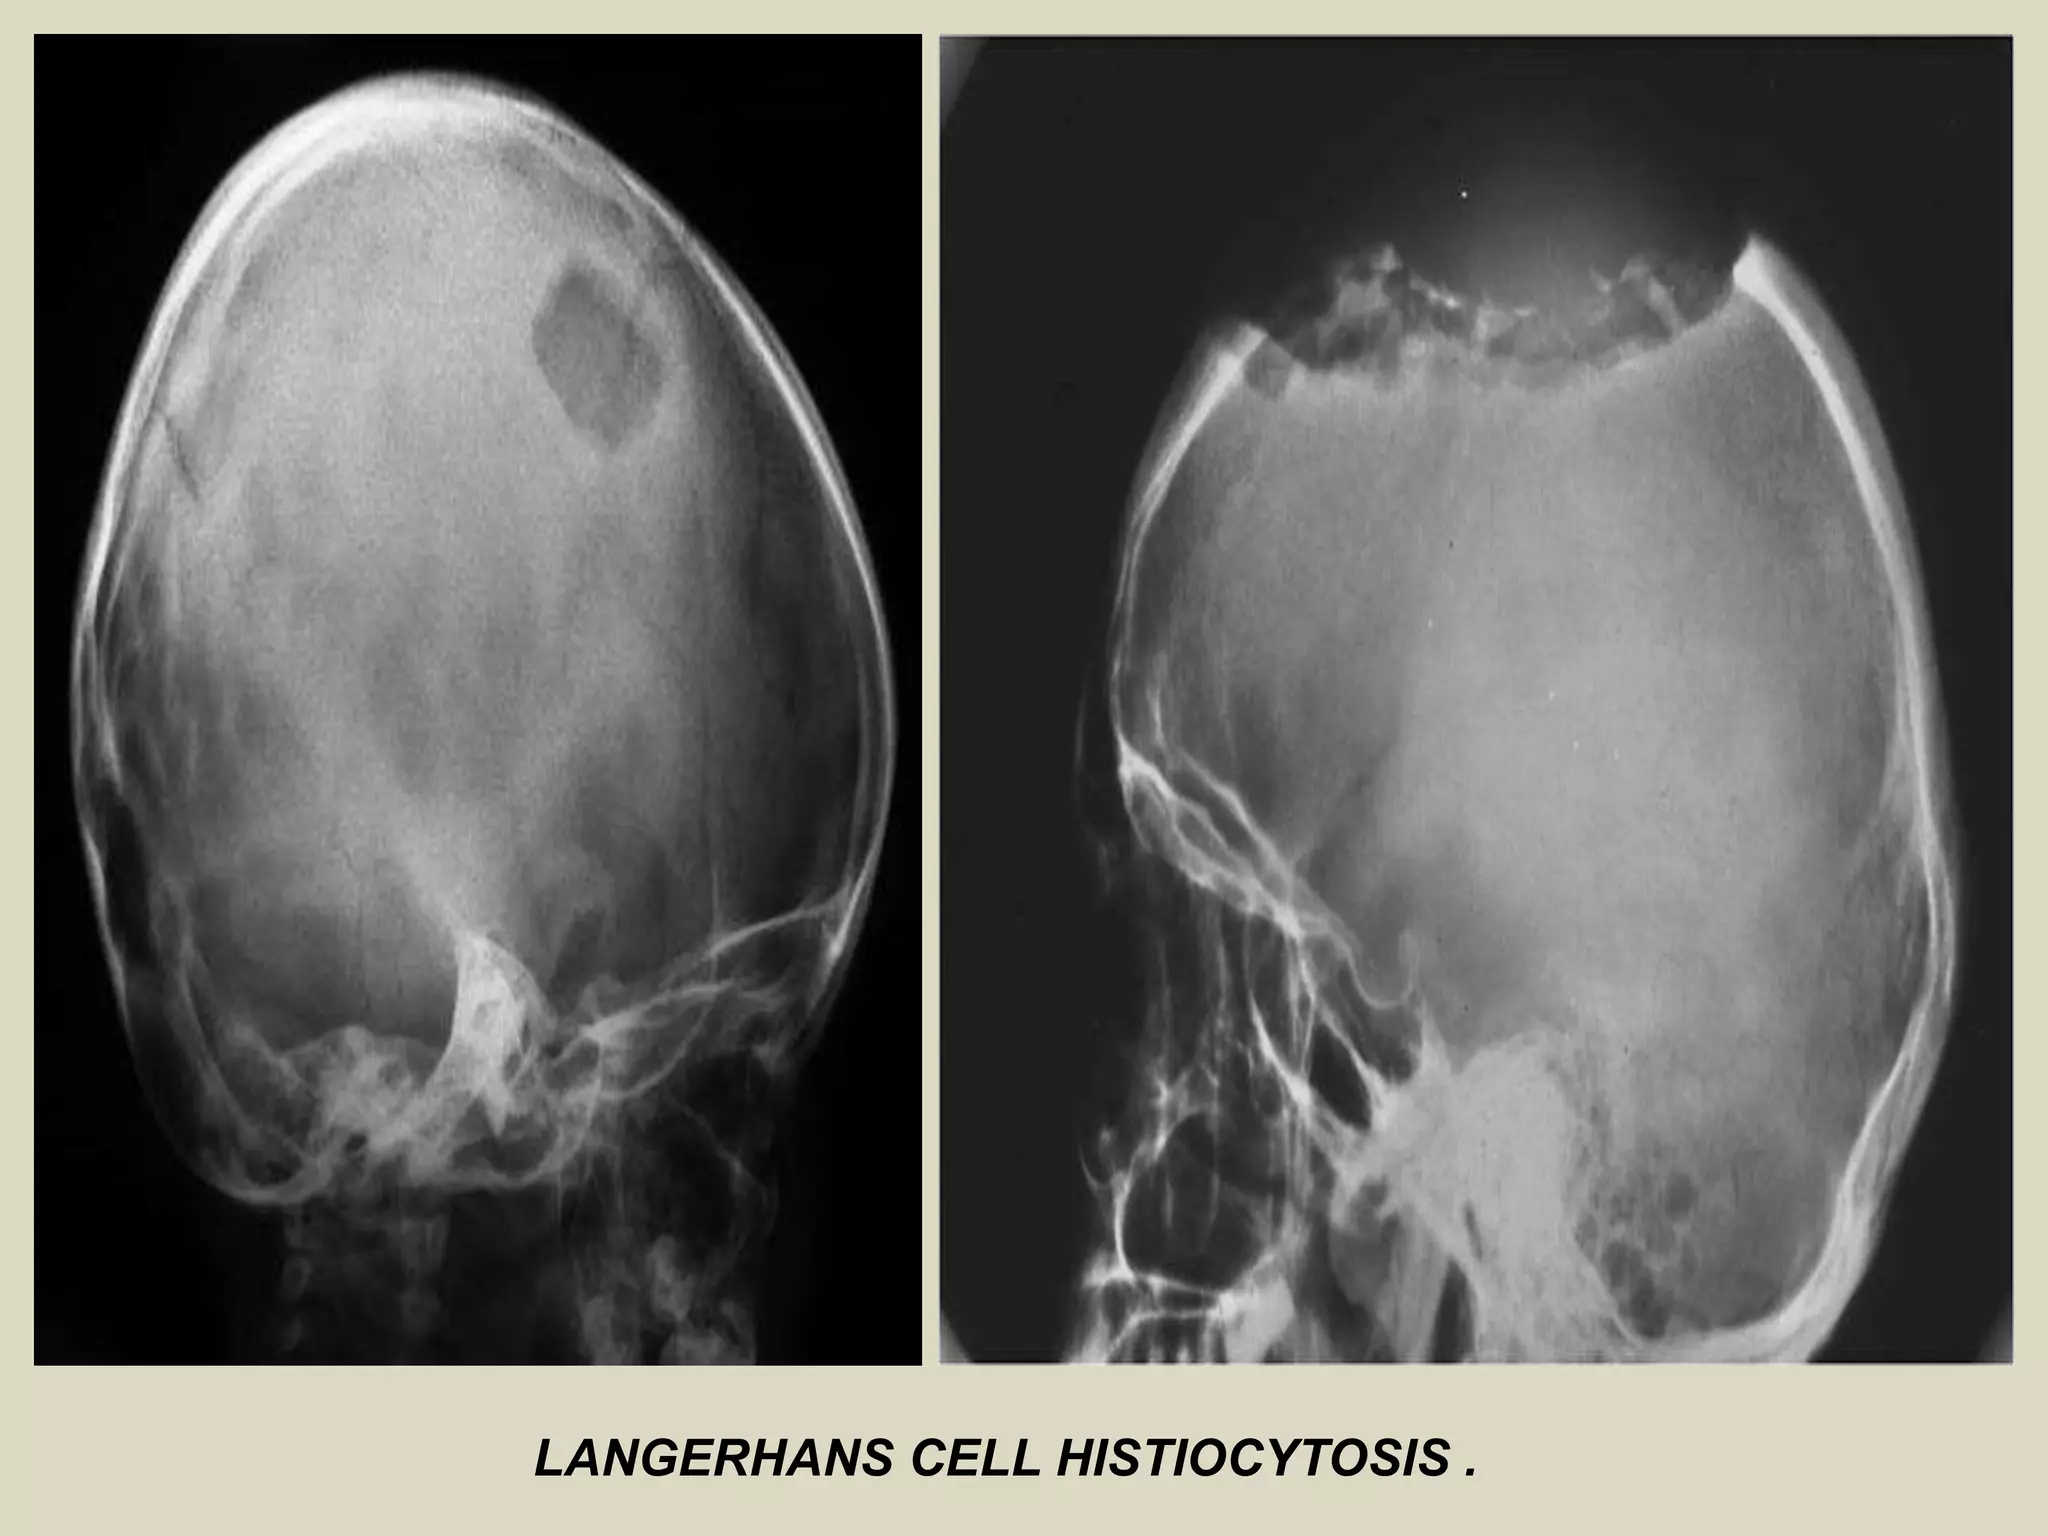

LANGERHANS CELL HISTIOCYTOSIS (EOSINOPHILIC GRANULOMA) OF BONE

Definition:

- Previously known as histiocytosis X, is an intraosseous mass of proliferating

Langerhans cells.

- Langerhans cells are dendritic cells that normally populate the skin, mucosal

surfaces, lymph nodes and other tissues where they function as specialized

antigen presenting cells.

- In Langerhans cell histiocytosis, the proliferating cells are monoclonal,

supporting the theory that the disease is neoplastic.

Epidemiology:

- LCH is relatively rare disorder, accounting for less than 1% of all osseous l

lesions.

- Age distribution is ranging from the first month to 8th decade of life with

80-85% of cases seen in patients under the age of 30, and 60% under the age

of 10.

- Males are affected twice as often as females.

Sites of involvement:

- Any bone may be involved, although there is predilection for LCH to involve

the bones of the skull, notably the calvarium.

- Other frequently involved sites include the femur, the bones of the pelvis,

and the mandible.

Imaging:

- LCH lesions are well defined and lytic on radiographs, however, in a minority

of cases may have ill-defined and permeative margins.

- Cortical involvement may elicit a periosteal reaction.

- Complete resolution of radiographic abnormalities may follow

treatment or occasionally occurs spontaneously.

LANGERHANS CELL HISTIOCYTOSIS.

LANGERHANS CELL HISTIOCYTOSIS .